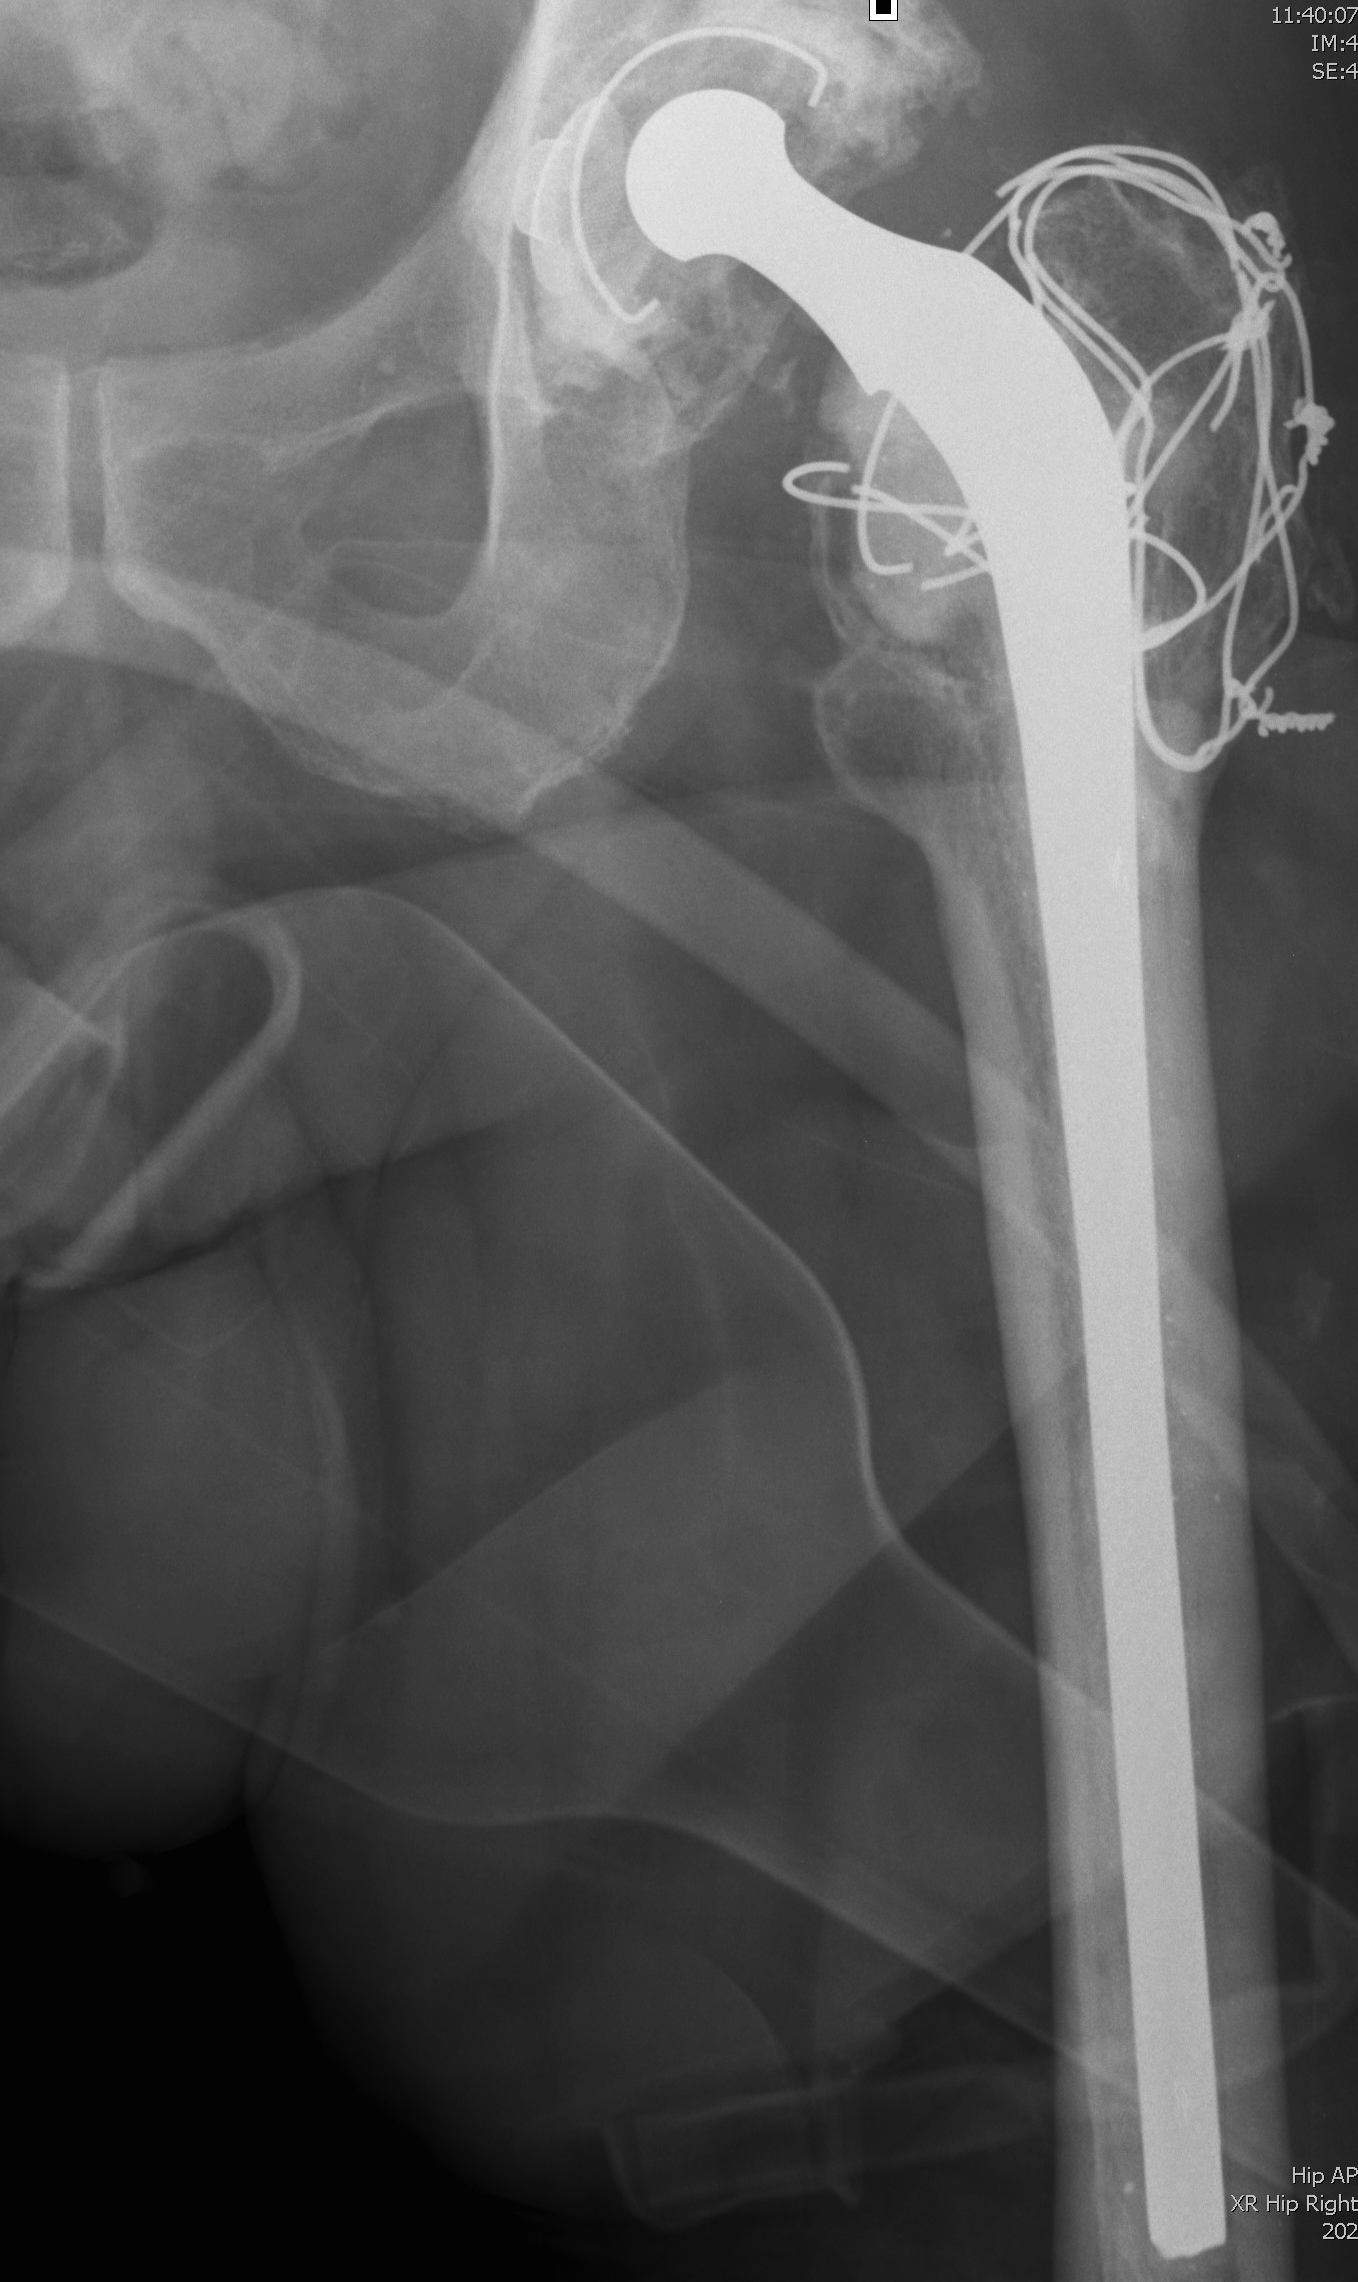

1. Long stem cemented revision femoral stem

2. Extensively porous coated diaphyseal fitting uncemented stem